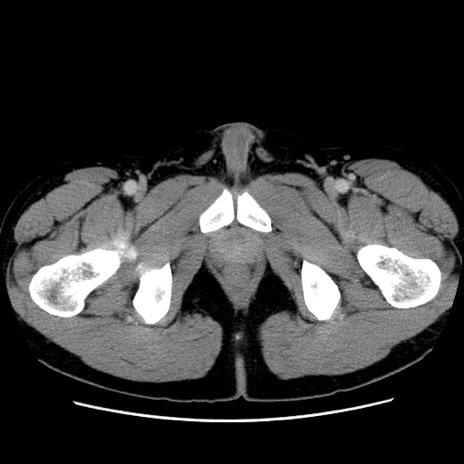

症例4(横断像)

【症例】30歳代男性

【主訴】腹痛、嘔吐

【現病歴】昨晩から突然の腹痛あり、その後嘔吐、軟便も出現。腹痛が改善しないため救急搬送となる。2日前にしめ鯖の食事歴あり。

【身体所見】意識清明、苦悶様、BP 135/90mmHg、BT 35.7℃、腹部:平坦、やや硬、心窩部〜臍部に自発痛、圧痛あり、筋性防御+、反跳痛-

【データ】WBC 8100、CRP 0.57